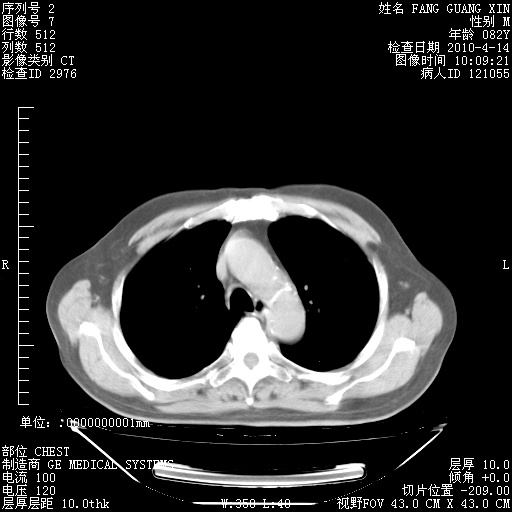

4月14日肺部CT

肺部CT平扫未见异常。